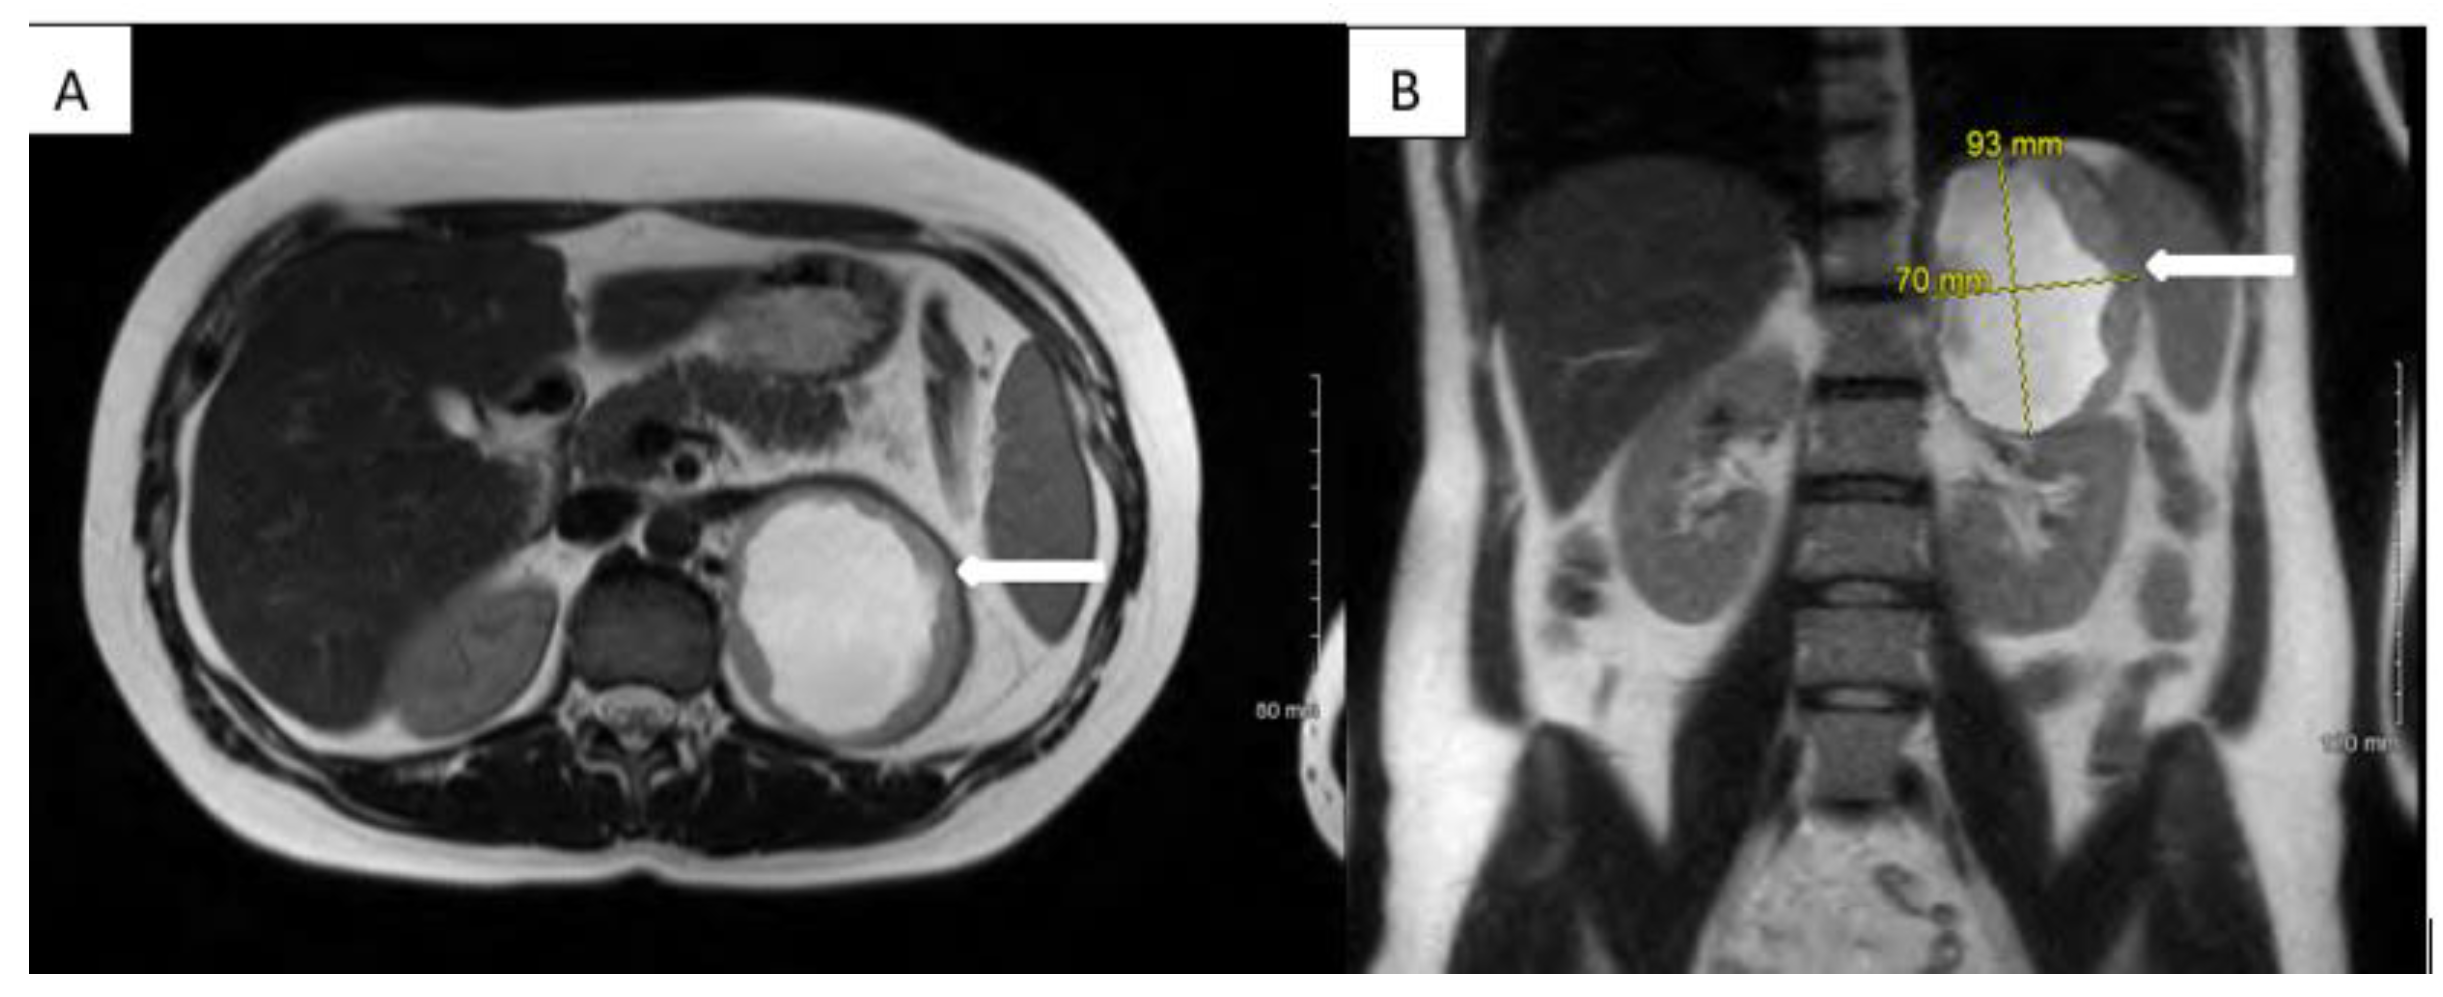

2. Case